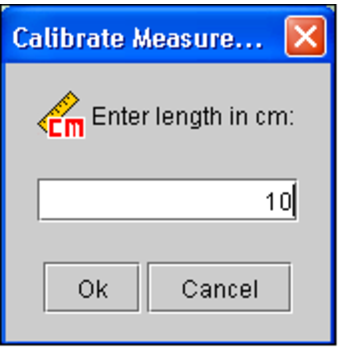

Click the Calibrate Measurement tool

.

.The Calibrate Measurement dialog appears.

-

Enter the length of the measurement in centimeters.

For example, in step 3 you can see that the drawn line corresponds to a length of 10 centimeters on the scale.

-

Click OK.